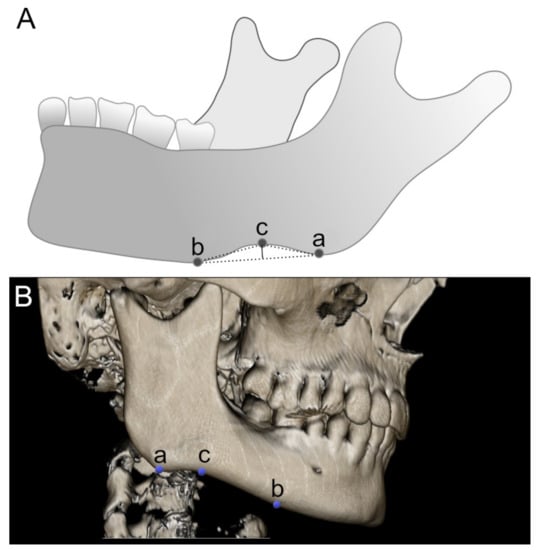

2.2. Measurement of the Antegonial Notch